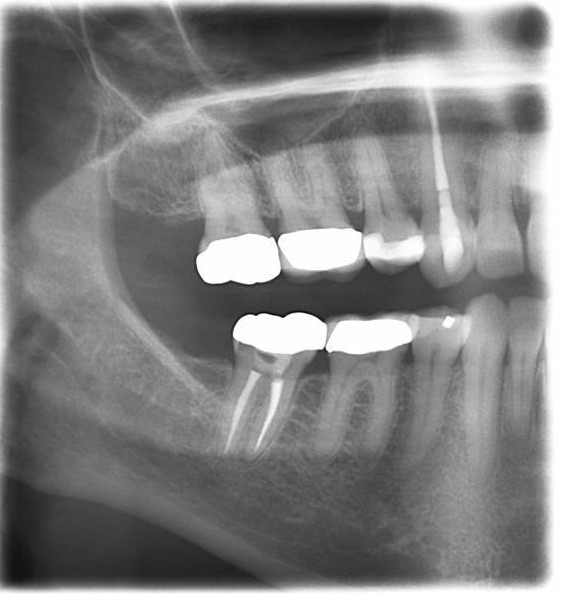

These images capture the upper and lower teeth’s biting surfaces and are commonly used to detect cavities between teeth.